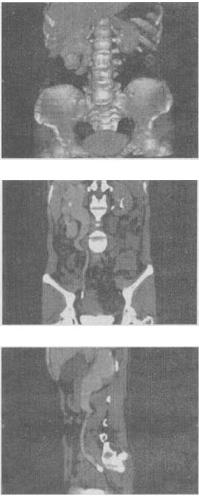

女,42岁,反复右下腹痛1个月,CT检查如图所示,下列诊断正确的是()。

A:右侧输尿管上段结石,其上方输尿管扩张积水

B:右侧输尿管中段结石,其上方输尿管扩张积水

C:右侧输尿管下段结石,其上方输尿管扩张积水

D:右侧输尿管下段结核,其上方输尿管扩张积水

E:右侧输尿管下段炎性狭窄,其上方输尿管扩张积水